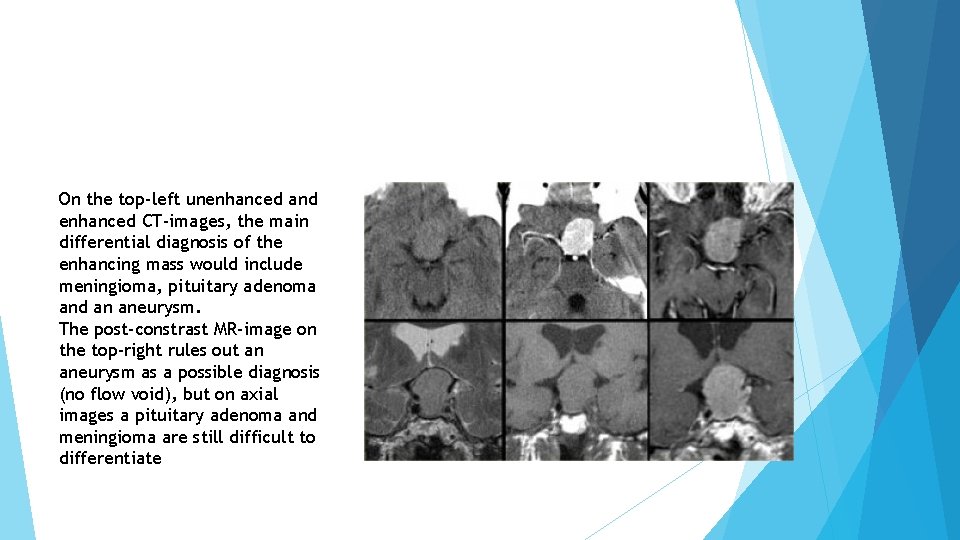

Meningioma The most common intracranial tumor in adults is the meningioma with 20% of occurring at the skull base. Meningiomas are almost always solid lesions, sometimes with a cyst on the edge. They can lift up the arachnoid a little bit and enhance uniformly as a general rule.

On the top-left unenhanced and enhanced CT-images, the main differential diagnosis of the enhancing mass would include meningioma, pituitary adenoma and an aneurysm. The post-constrast MR-image on the top-right rules out an aneurysm as a possible diagnosis (no flow void), but on axial images a pituitary adenoma and meningioma are still difficult to differentiate

Notice the spread of the lesion along the meninges. The epicentre of the lesion is above the sella.

Note the compresses pituitary gland There is no evidence of cystic change or hemorrhage